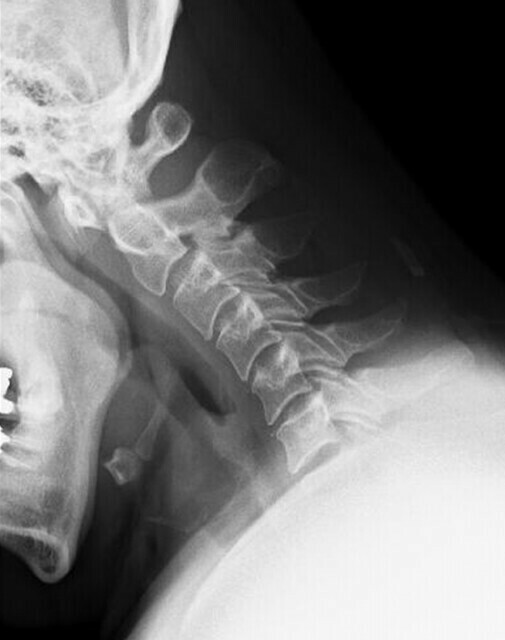

ストレートネックは元に戻りますか?どこに行けばいですか? -3続きを読む